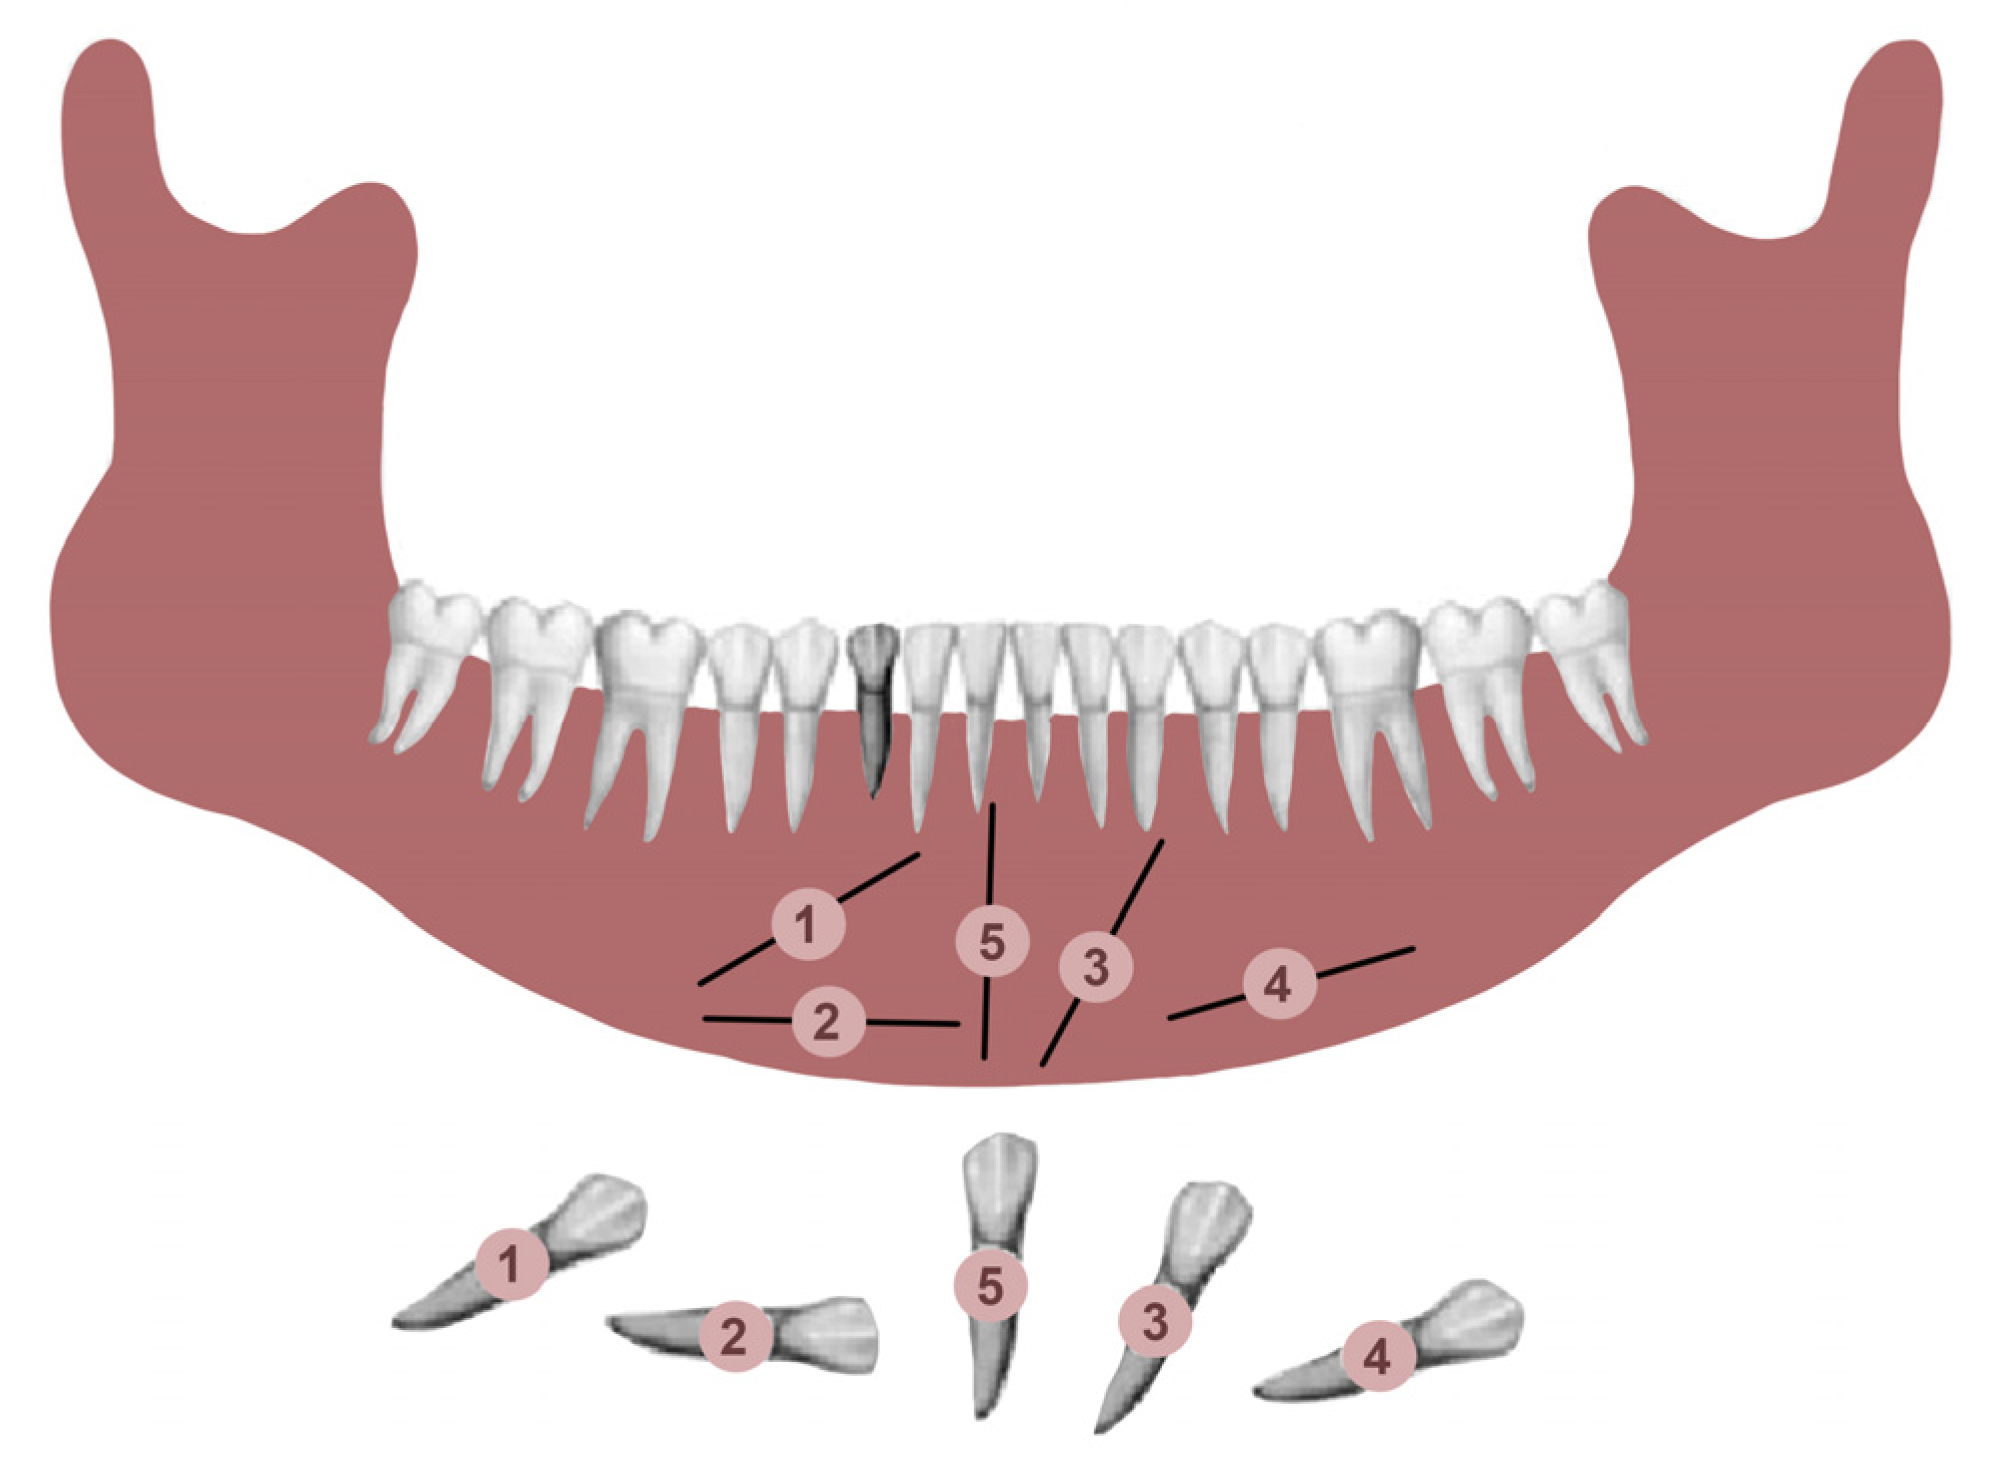

Transmigrated mandibular canines were classified according to Mupparapu’s classification [19]. Mupparapu used five criteria to classify the transmigrated mandibular canines into five types. This classification was based on their migratory pattern, the inclination of the longitudinal axis of the canine, the final position inside the mandible, and the relation of the canine crown with adjacent teeth, the midline, and the contralateral erupted canine (Figure 1) [19].

Figure 1.

Diagrammatic representation of the 5 patterns of transmigration, with a retained deciduous right mandibular canine according Mupparapu.

Type 1: the canine is positioned mesioangularly across the midline, labial or lingual to the anterior teeth, and the crown portion crosses the midline.

Type 2: the canine is impacted horizontally near the inferior border of the mandible below the apices of the incisors.

Type 3: the canine has erupted either mesially or distally to the opposite canine.

Type 4: the canine is horizontally impacted near the inferior border of the mandible below the apices of either premolars or molars on the opposite side.

Type 5: the canine is positioned vertically in the midline, with the long axis of the tooth crossing the midline.